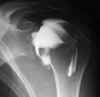

Arthrografie

Een arthrografie wordt uitgevoerd om een gewrichtsholte te visualiseren. Hiervoor wordt een contrastmedium in het gewricht gespoten. Vaak wordt er eveneens lucht ingespoten. Dit om een duidelijker beeld te verkrijgen van de kraakbeenoppervlakken van de gewrichten. Na een aantal opnames op de conventionele radiologie wordt er een CT-scan gedaan om het gewricht beter nog te kunnen evalueren. Plaatselijke verdoving kan gegeven worden maar is niet de regel, denk erom dat er steeds een prik gegeven wordt, vaak is voor de punctie maar een prik nodig, met de verdoving worden het er twee.

Een arthrografie kan ook gebeuren ter voorbereiding van een MRI onderzoek.  De indicaties en de de voor- en nazorg blijven indentiek.

Indicaties:

Letsels aan pezen en/of ligamenten van het gewricht

Letsels van het gewrichtskapsel

Ontwrichting

Bot of kraarbeenletsels

Gewrichtsmuizen (dit zijn kleine stukjes bot die los in het gewricht voorkomen)